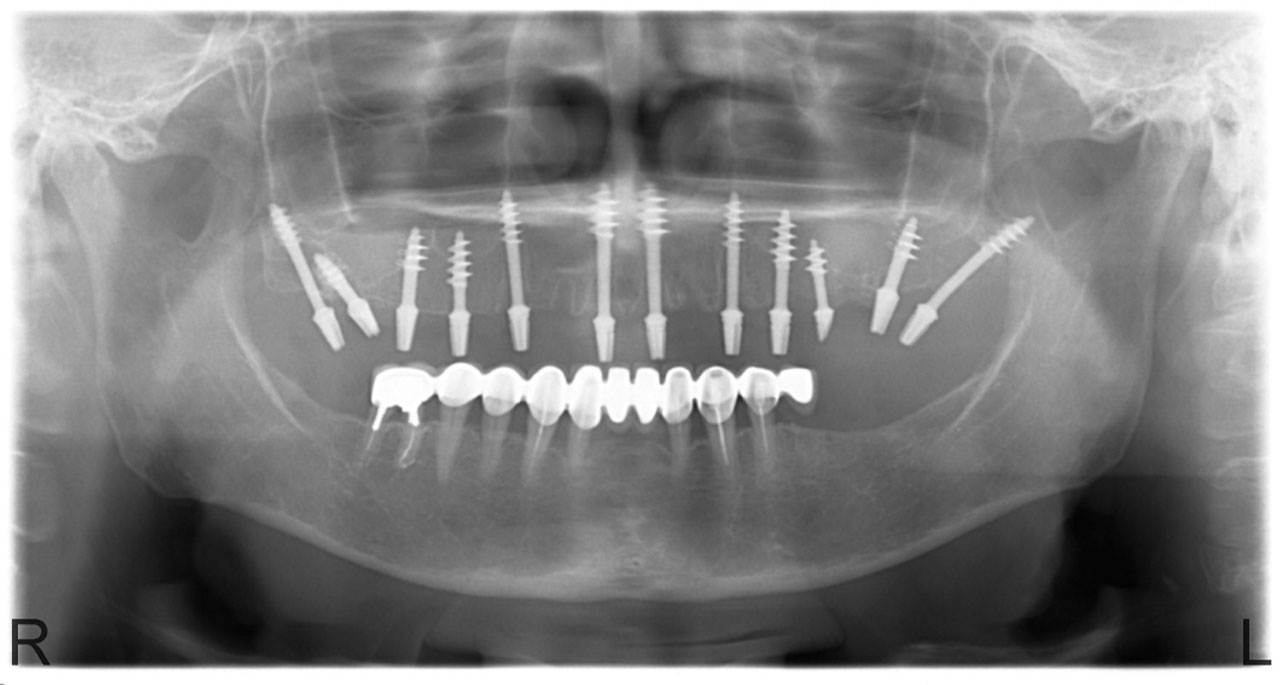

• esettanulmany-03

Imlantáció után,bal oldalon már a végleges hidakkal, jobb oldalon még csak az implantátumok.

• esettanulmany-14

Alsó- felső fogatlan állcsont teljes implantációs helyreállítása.